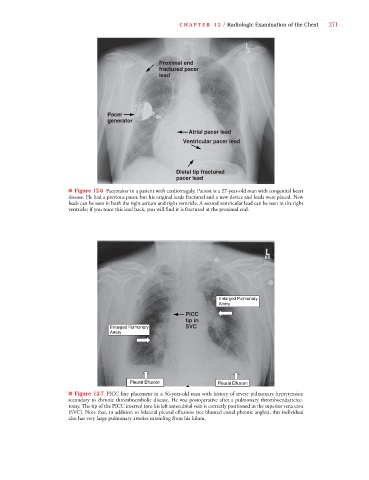

C HAPTER 12 / Radiologic Examination of the Chest 271

Proximal end

fractured pacer

lead

Pacer

generator

Atrial pacer lead

Ventricular pacer lead

Distal tip fractured

pacer lead

■ Figure 12-6 Pacemaker in a patient with cardiomegaly. Patient is a 27-year-old man with congenital heart

disease. He had a previous pacer, but his original leads fractured and a new device and leads were placed. New

leads can be seen in both the right atrium and right ventricle. A second ventricular lead can be seen in the right

ventricle; if you trace this lead back, you will find it is fractured at the proximal end.

Enlarged Pulmonary

Artery

PICC

tip in

Enlarged Pulmonary SVC

Pleural Effusion Pleural Effusion

■ Figure 12-7 PICC line placement in a 56-year-old man with history of severe pulmonary hypertension

secondary to chronic thromboembolic disease. He was postoperative after a pulmonary thromboendarterec-

tomy. The tip of the PICC inserted into his left antecubital vein is correctly positioned in the superior vena cava

(SVC). Note that, in addition to bilateral pleural effusions (see blunted costal phrenic angles), this individual

also has very large pulmonary arteries extending from his hilum.